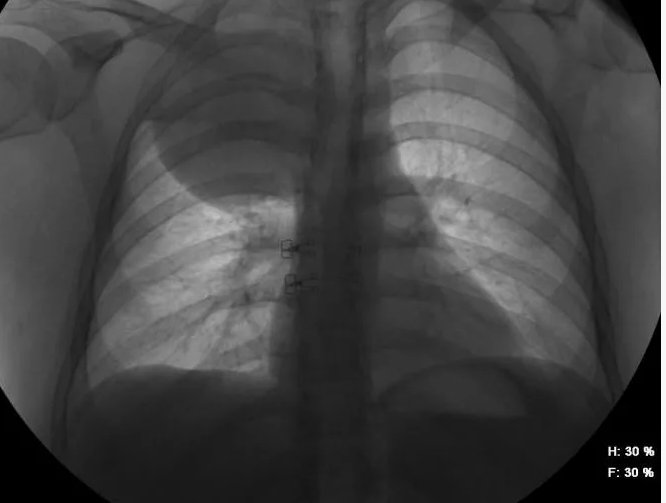

Изучение проблемы низкого качества рентгенограмм на Вашем оборудовании.

Мобильный рентгенаппарат + оцифровщик. Получение рентгеновского изображения на экране ноутбука. Вариант за 1,4 миллиона рублей под ключУРА